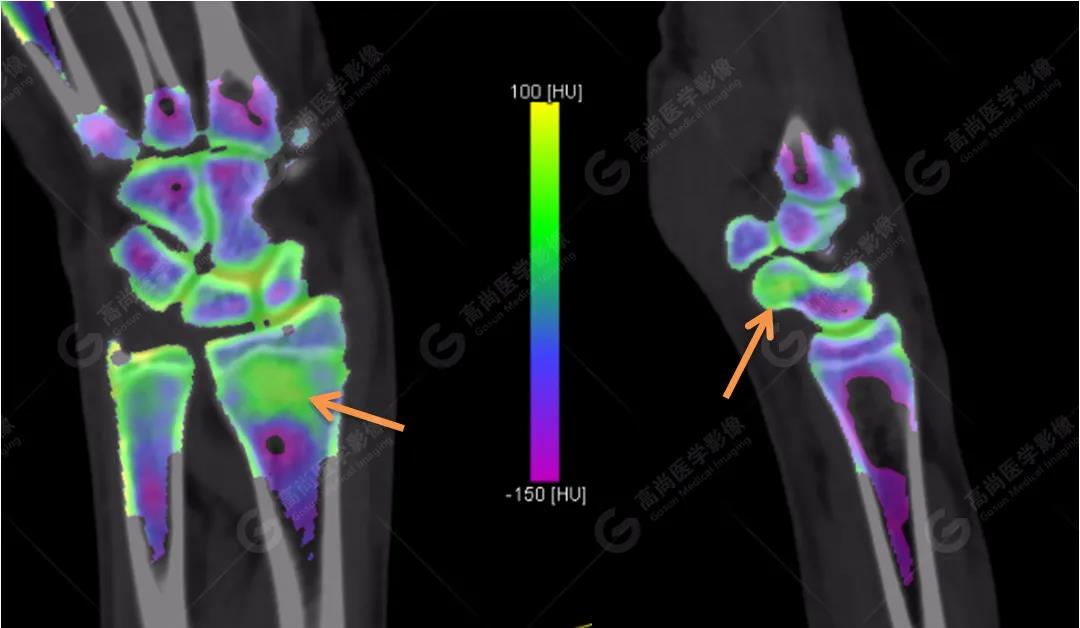

3、雙能CT骨髓成像(雙能虛擬去鈣圖像)

高尚醫(yī)學(xué)影像診斷中心的Flash雙源CT可以利用雙能量骨髓成像來顯示骨骼內(nèi)的骨髓水腫,而外傷性的骨髓水腫往往提示骨挫傷或小梁微骨折。重建一下雙能虛擬去鈣骨髓圖像,進(jìn)一步排除骨挫傷、微骨折。

雙能CT骨髓成像圖上發(fā)現(xiàn)了左側(cè)橈骨遠(yuǎn)端和右側(cè)舟狀骨骨髓水腫(箭頭所示),進(jìn)一步查體這兩處骨髓水腫剛好與患者的局部壓痛點(diǎn)相一致。